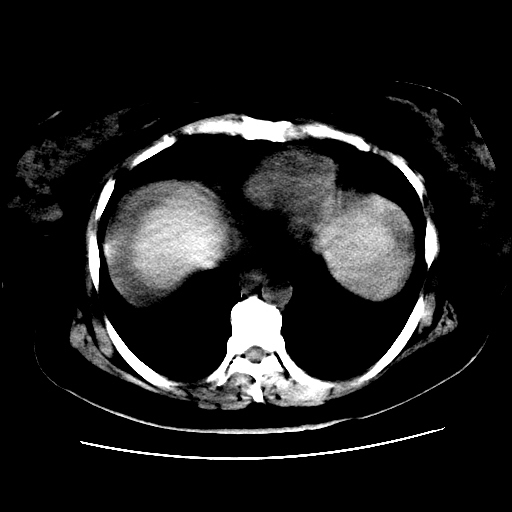

f,45y.怀孕4月晕倒,b超提示死胎,有手术结果,请展开讨论后明天告诉。

膈下-肠间隙内见气体密度影,子宫轮廓显示不清,宫腔-腹腔积液,首选考虑---子宫破裂出血。

1)宫腔妊娠。2)子宫破裂出血,腹腔及盆腔积血。

怀孕4个月晕倒,病史就这么简单?有没有腹痛呢?腹腔内有没有气体?窗宽太窄了脂肪组织与气体已不好分。如果有气体,那就是空腔脏器穿孔,如胃肠穿孔。如没有气体,就考虑子宫破裂或宫外孕破裂。正常怀孕子宫破裂很少见,有可能是宫外孕。极有可能是残角子宫怀孕破裂。腹腔怀孕破裂也有可能。

感谢同行们的高见。手术结果:子宫破裂出血。

我们的诊断是:腹、盆腔积液(考虑腹盆腔脏器破裂出血);宫腔妊娠。让人纳闷的是当时我们没有经验,现在回头看看分析:4月宫腔妊娠:1、洋膜囊不可能紧贴胎体这么小;2仔细看看子宫后壁肌层模糊不清;3腹、盆腔液体来源原因?4、45岁高龄妊娠有晕倒。由此可大胆诊断:宫腔妊娠子宫破裂出血。